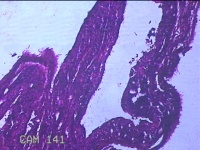

右侧卵巢囊肿

性别

女

年龄

26岁

临床诊断

一般病史

下腹痛3天。

标本名称

大体所见

灰白暗红色囊壁样组织2.5x1.5x0.3cm一块,表面糜烂,因已切开,囊内容物已流失,囊壁厚0.1cm。